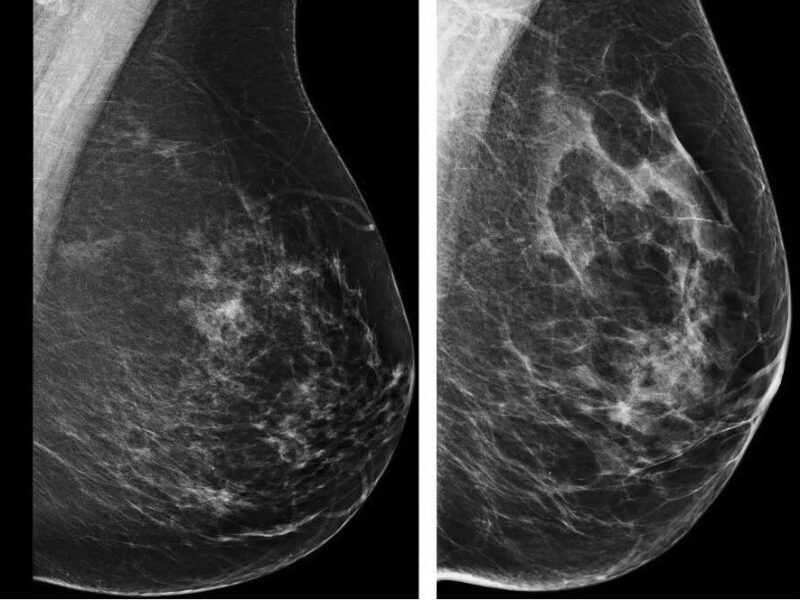

Dans le dépistage du cancer du sein, l’IRM mammaire doit être employée avec pertinence et discernement. C’est le message qu’a voulu faire passer Aurélie Jalaguier-Coudray lors d’une session des Journées francophones de radiologie 2018 consacrée à cette modalité, dimanche 14 octobre. Un rendez-vous préparé par la Société française d’imagerie de la femme (SIFEM). « L’IRM ne peut pas et ne doit pas résoudre tous vos problèmes. Le couple mammographie et échographie suffit la plupart du temps », a répété la spécialiste, en rappelant le principe de base de cette modalité : « Si l’IRM montre une anomalie, il faut faire une biopsie puisqu’elle a une haute sensibilité. Si elle ne montre rien, on reclasse le bilan parce que l’IRM présente une haute valeur prédictive négative. »